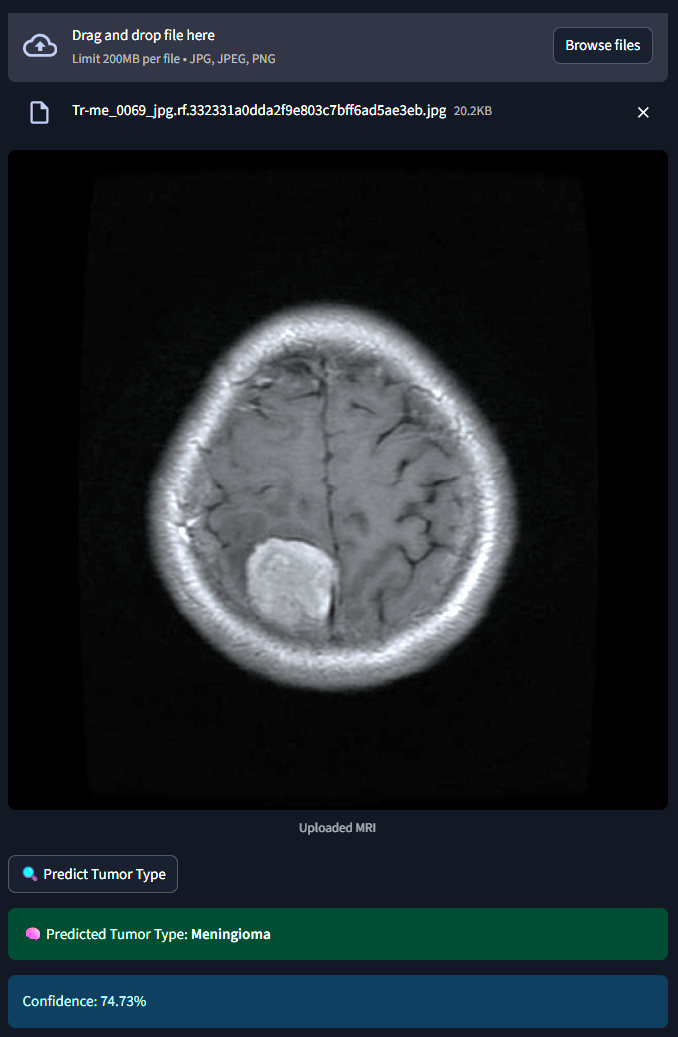

The system classifies MRI brain scans into one of four categories - Glioma, Meningioma, Pituitary Tumor or No Tumor. It uses both a Custom Convolutional Neural Network (CNN) and MobileNetV2 Transfer Learning for classification. An interactive Streamlit web app allows users to upload MRI images and receive real-time tumor predictions with probability scores.

1) Dataset :- 2,443 MRI images labeled and categorized by medical experts. 2) Preprocessing :- Used ImageDataGenerator for rescaling, rotation, zoom and flipping to augment limited data. 3) Model 1 (Custom CNN) :- Built from scratch with 3 convolutional layers, dropout and softmax classification. 4) Model 2 (MobileNetV2) :- Fine-tuned transfer learning model using pretrained ImageNet weights. 5) Training :- Used callbacks like EarlyStopping and ModelCheckpoint to optimize training and avoid overfitting. 6) Evaluation :- Tracked model performance using confusion matrix, accuracy/loss plots, and classification reports. 7) Deployment :- Developed a Streamlit web app for real-time image classification and visualization.